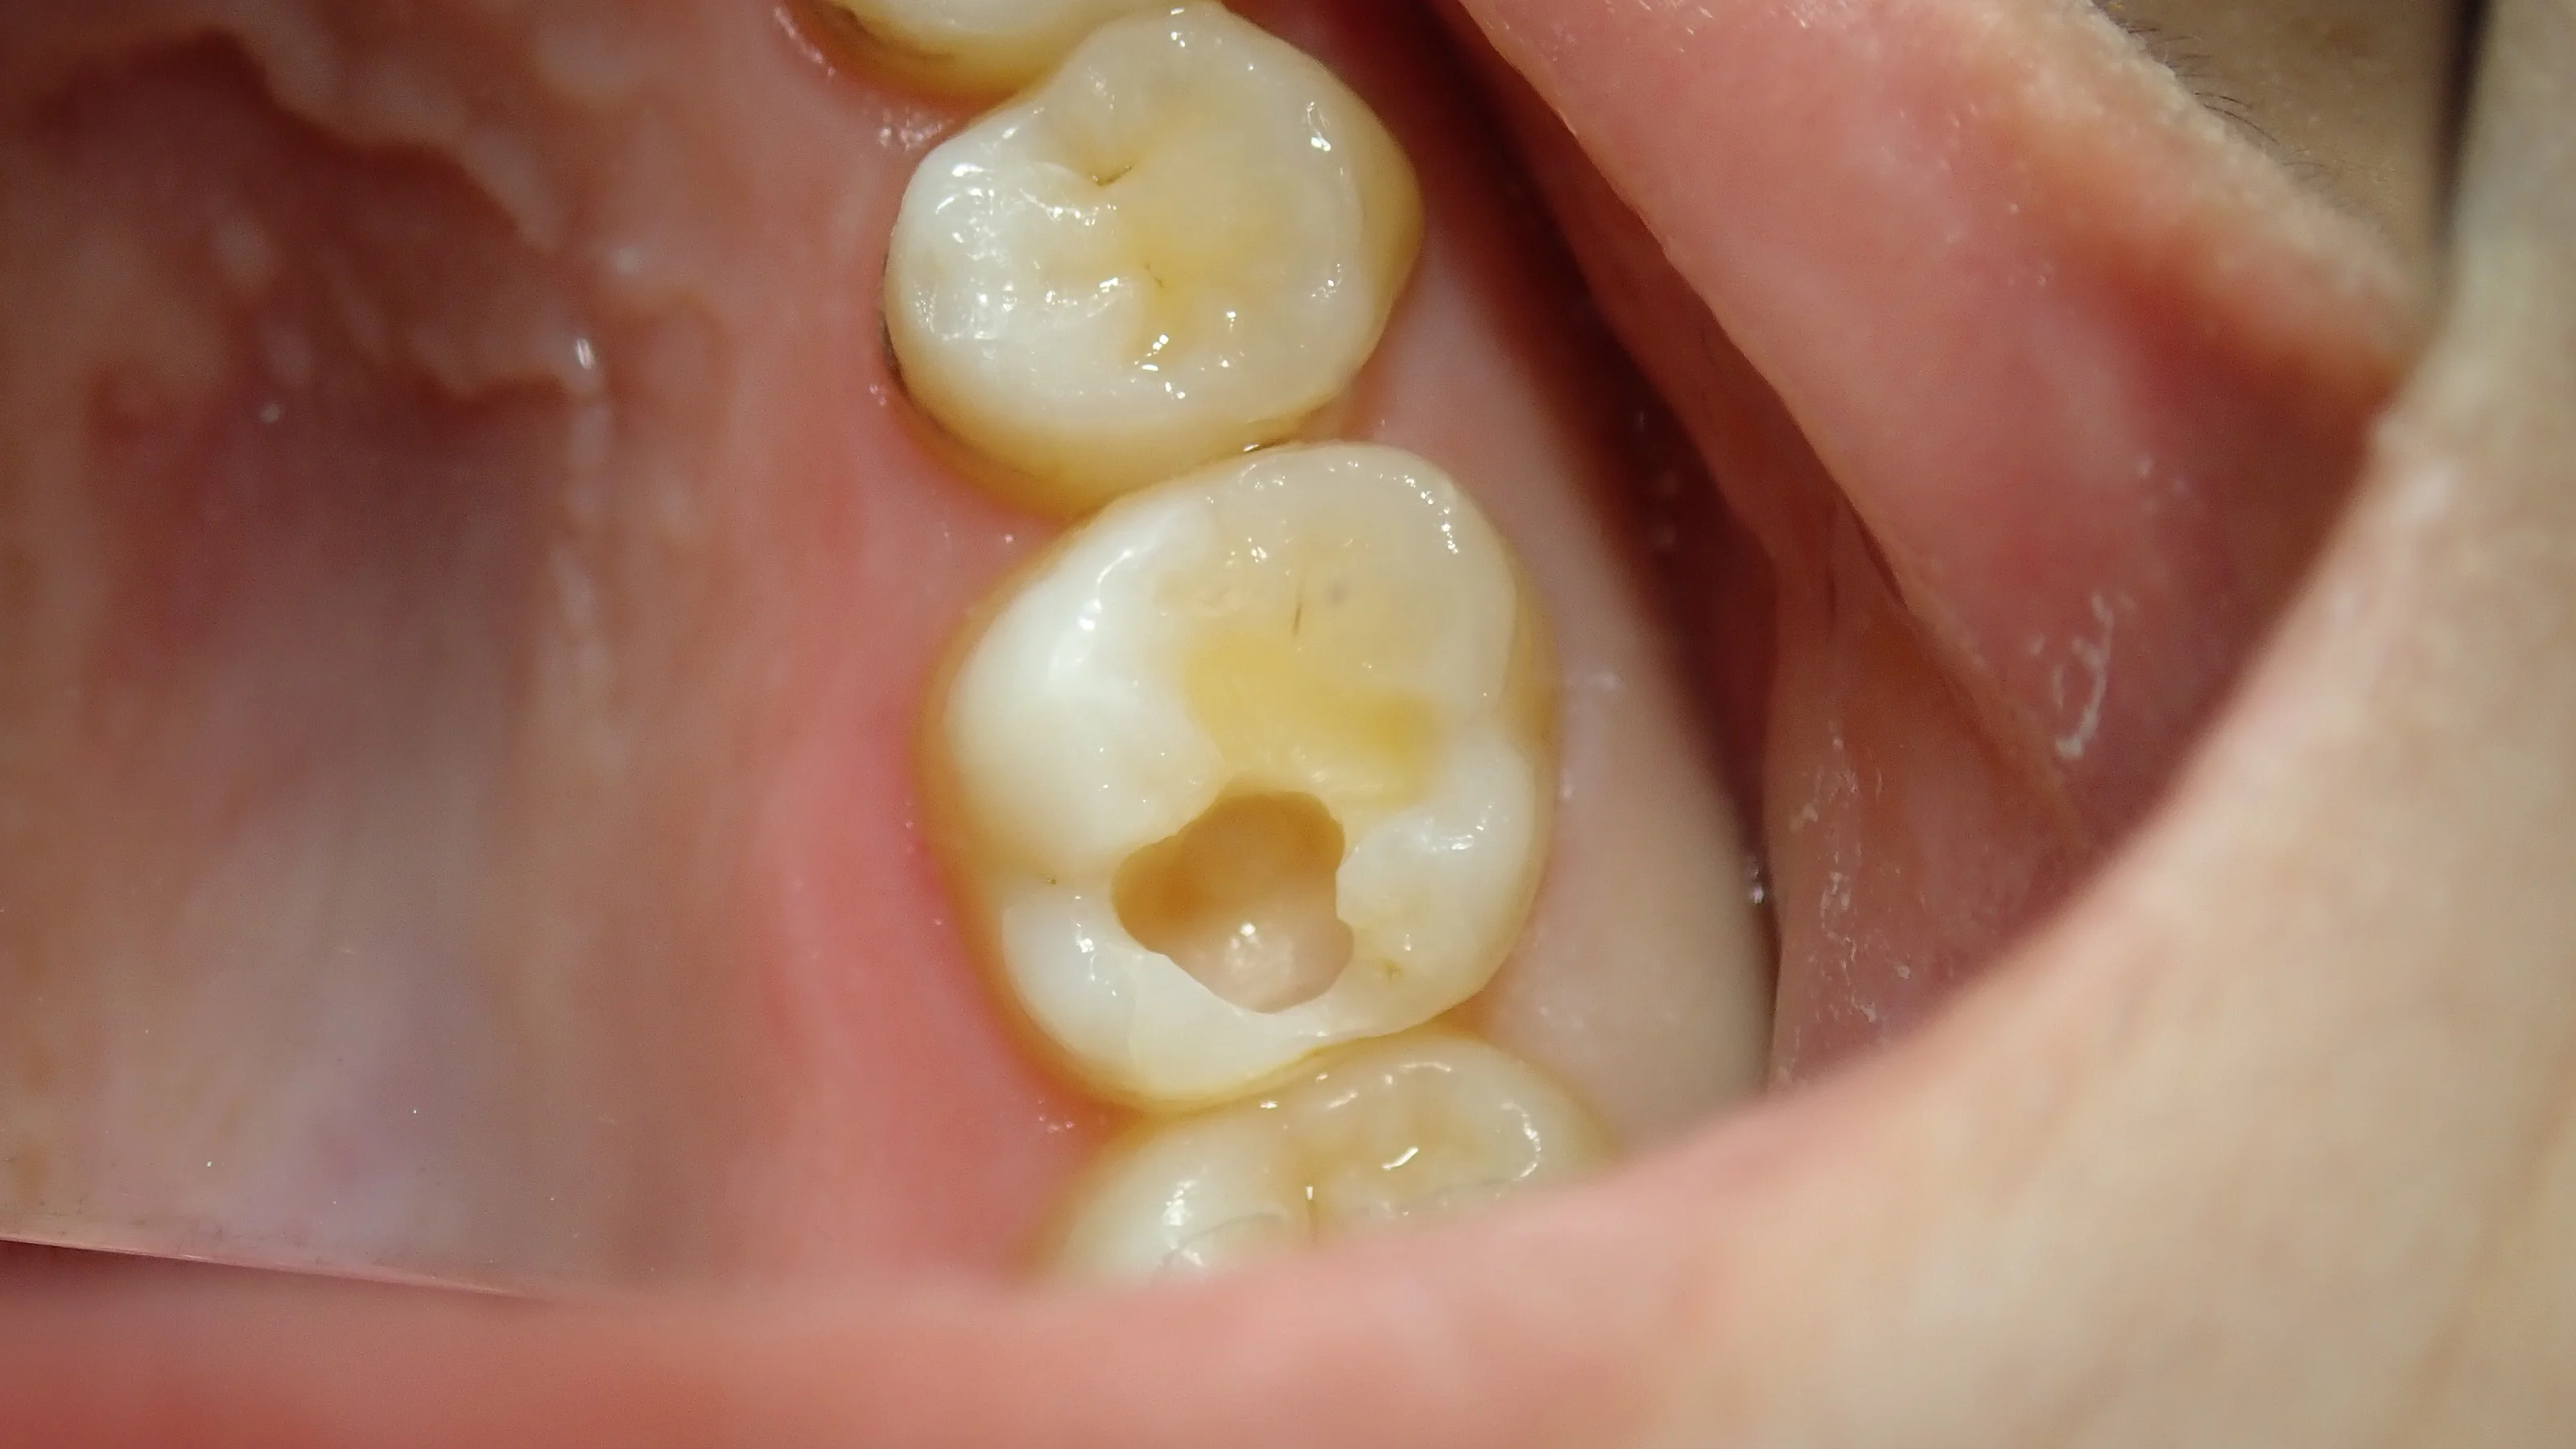

完全に虫歯を取りきると・・・

ものすごく大きい状態でした。

良くも悪くも変に削られておらず、歯を非常に多く残すことが出来たため、そのまま保険内でコンポジットレジンで治療させてもらいました。